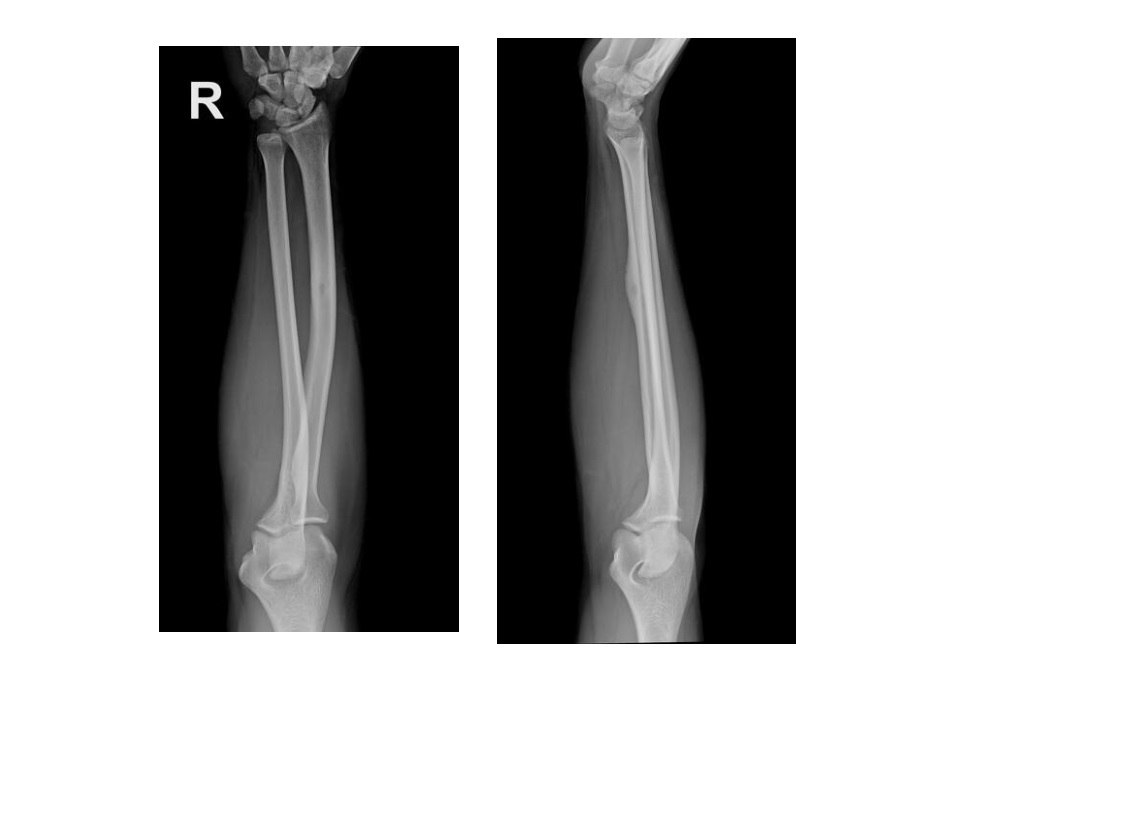

Features of hypertrophic osteoarthopathy

Periosteal reaction, usually along shafts of tubular bones in extremities Generally symmetrical Location Tibia, fibula, radius, ulna are most frequent Less common in phalanges 3-phase bone scan Typically linear symmetric ↑ uptake along margins of long bones: parallel track sign, tram line sign, or double stripe sign